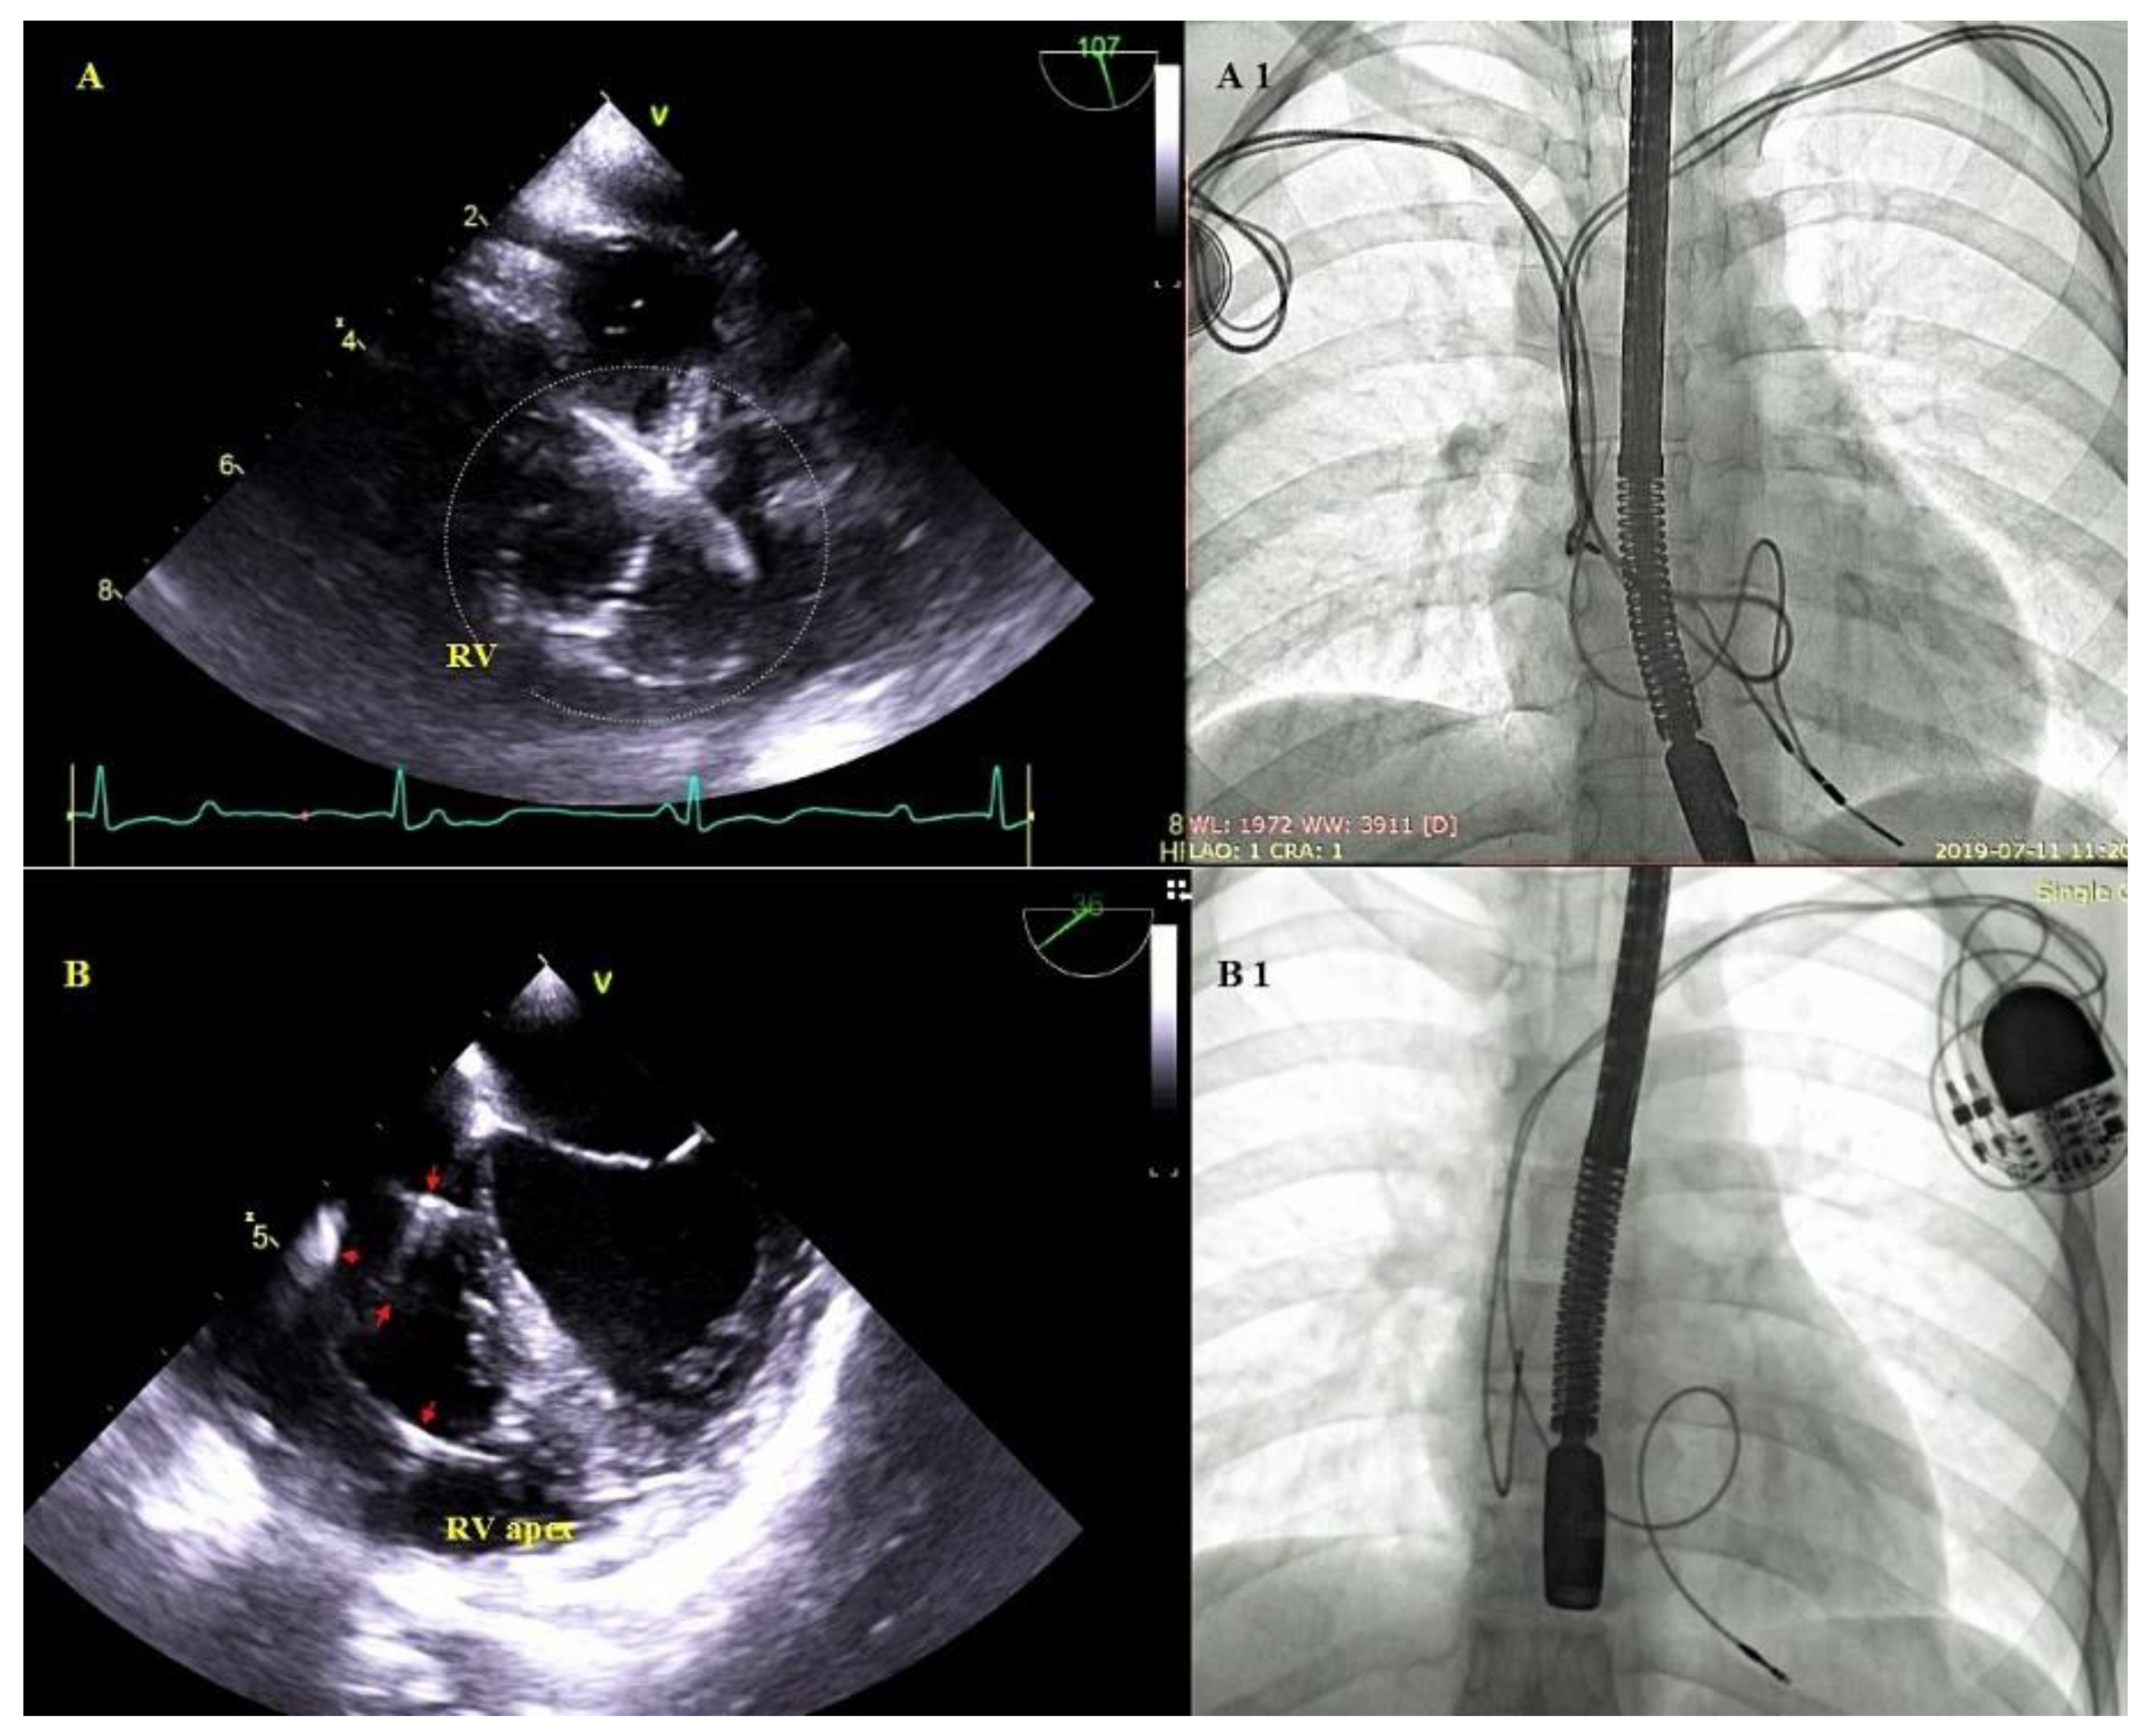

2.5. Echocardiographic Findings Associated with Endocardial Leads: Definition and Classification According to the Anatomy and Characteristic Features